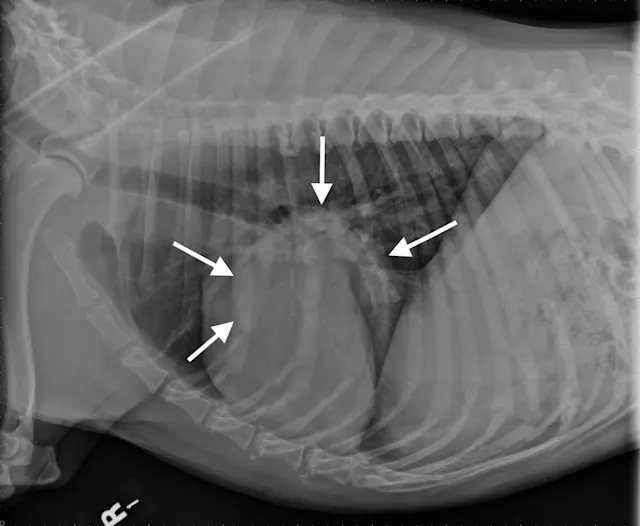

Figure 1A

Canine lung tumor

In these 3-view thoracic radiographs of an 8-year-old neutered male boxer with a lung tumor, a large soft tissue mass visibly extends to the lung lobe margins, nearly causing complete consolidation of the right middle lung lobe. Several closely spaced air bronchograms at the caudal margin of the mass are consistent with atelectasis caused by the expansile nature of the mass (Figure 1A; arrows). The apparent right mediastinal shift (ie, shifting of the cardiac silhouette to the right) in the ventrodorsal view (Figure 1C) is, at least in part, due to a moderate degree of patient rotation.

This patient underwent a right intercostal thoracotomy and lung lobectomy for tumor resection. On exposure of the thoracic cavity during surgery, it was found that the tumor was in contact with the right side of the heart, and, accordingly, occasional ventricular arrhythmias (ie, 3-4 per minute) were noted. A narrowly excised low-grade pulmonary carcinoma was confirmed via histopathology.